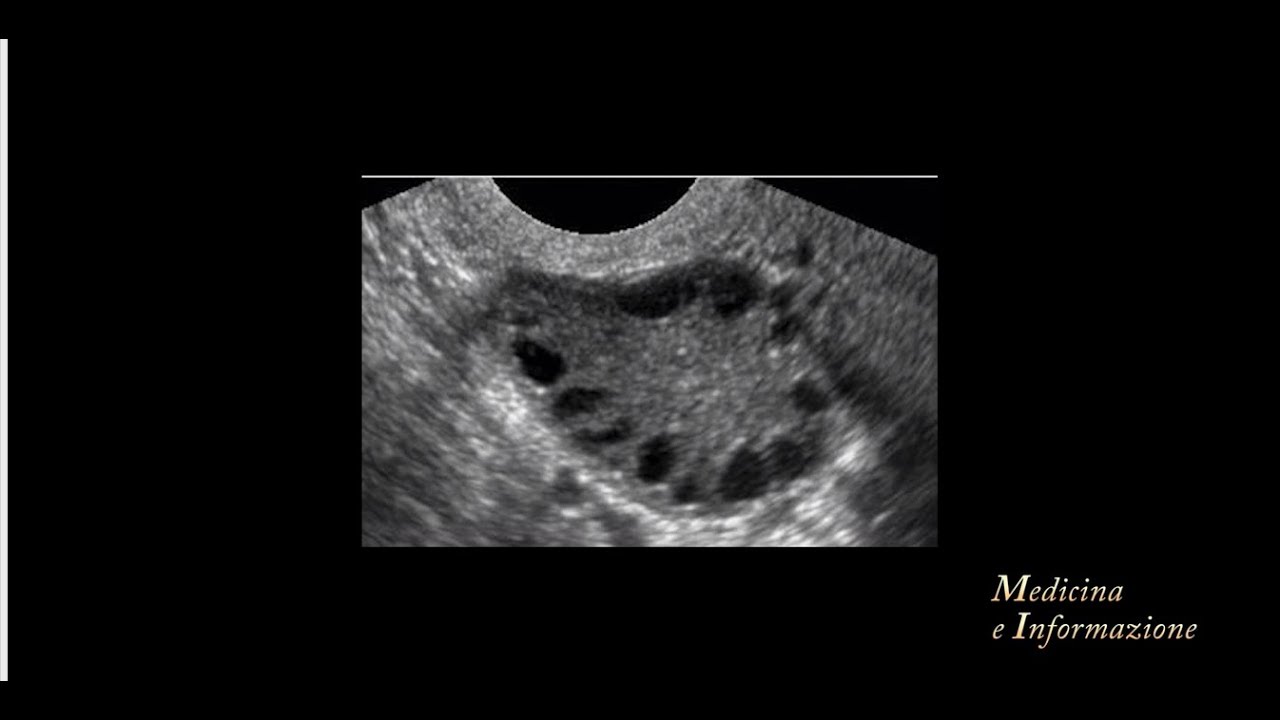

In questo video affronto un tema ricorrente per le donne affette da sindrome dell'ovaio policistico: l'irsutismo. Infatti ovaio policistico e peli in eccesso sono un binomio che spesso va di pari passo. Mi è capitato più volte di vedere online che venissimo definite "donne con la barba".